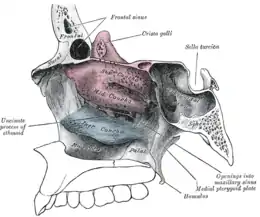

It has been proposed, that the airflow in ENS patients is changed so that most of the air flows through the middle meatus, compared to most of the air flowing through the inferior meatus in healthy individuals. This can be corrected via inferior meatus augmentation (IMAP surgery).[19]

Four types have been proposed:[22]

- ENS-IT: Inferior turbinate (IT) was fully or partially resected

- ENS-MT: Middle turbinate (MT) was fully or partially resected

- ENS-both: Both the IT and MT were both at least partially resected

- ENS-type: Patient appears to have adequate turbinate tissue but suffers ENS symptoms due to damage to the mucosal surface of the turbinates.